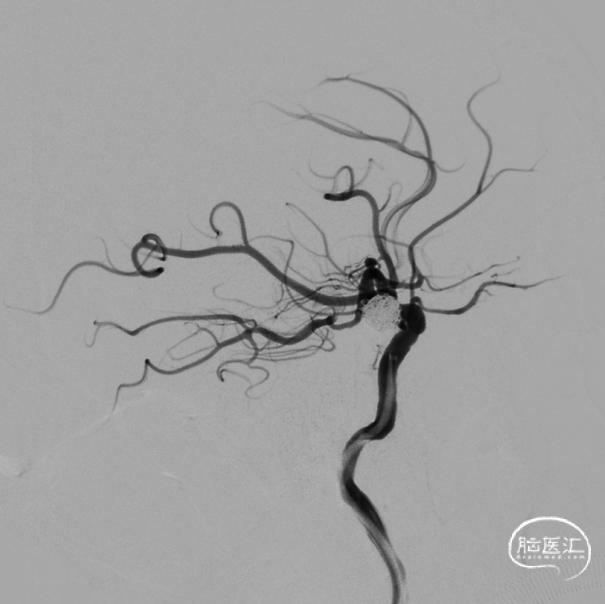

2022-12-06 DSA:左侧颈内动脉后交通动脉段动脉瘤,大小约12.46mm*8.76mm,葫芦型。

动脉瘤的形态:不规则、葫芦状。

动脉瘤大小(mm):长:12.46 宽:8.76

动脉瘤颈宽度(mm):4.56

载瘤动脉直径(mm):远端:3.77 近端:4.10